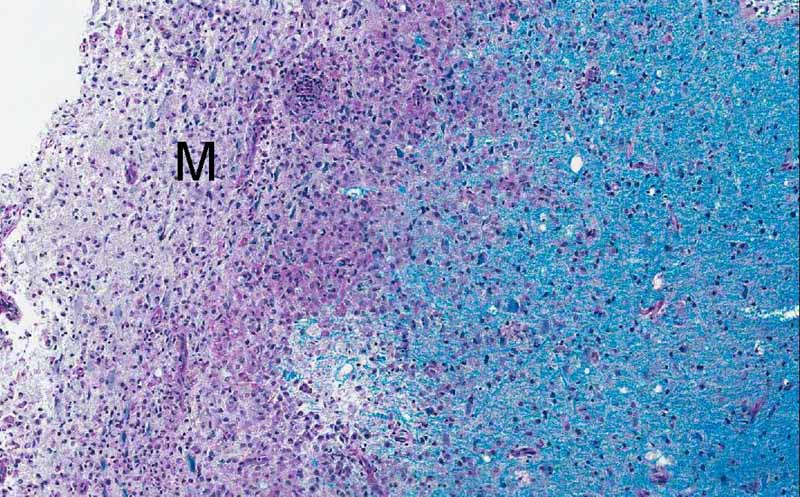

Luxol fast blue & PAS

Luxol Fast Blue and PAS Stain: Luxol fast blue demonstrates normal myelin in blue. This photo is taken from area 1 and you can see that the area infiltrated by macrophages does not have much myelin but the area that is not infiltrated by macrophages has myelin. This indicates a lost of myelin. This is a classic histopathologic finding. The macrophages are scavengers that remove the degraded myelin. The PAS stain is a counter stain but it has the ability to stain up the lysosomes in macrophages red.